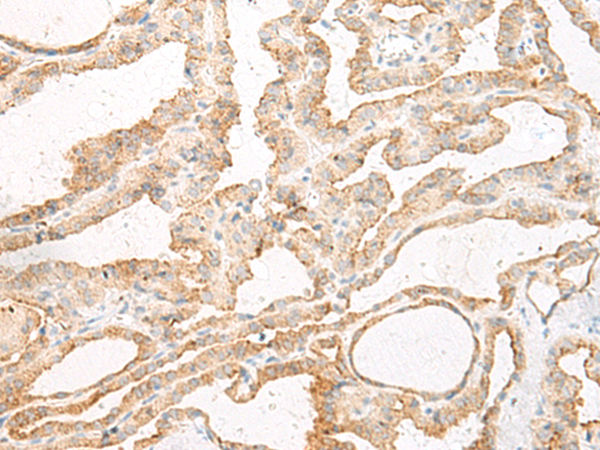

分类: 科研抗体货号: P13479别名: C5L2; GPF77; GPR77应用: IHC反应种属: Human